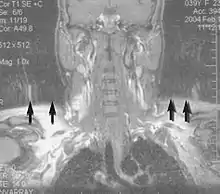

A motion artifact is one of the most common artifacts in MR imaging.[2] Motion can cause either ghost images or diffuse image noise in the phase-encoding direction. The reason for mainly affecting data sampling in the phase-encoding direction is the significant difference in the time of acquisition in the frequency- and phase-encoding directions.[1] Frequency-encoding sampling in all the rows of the matrix (128, 256 or 512) takes place during a single echo (milliseconds). Phase-encoded sampling takes several seconds, or even minutes, owing to the collection of all the k-space lines to enable Fourier analysis. Major physiological movements are of millisecond to seconds duration and thus too slow to affect frequency-encoded sampling, but they have a pronounced effect in the phase-encoding direction. Periodic movements such as cardiac movement and blood vessel or CSF pulsation cause ghost images, while non-periodic movement causes diffuse image noise (Fig. 1). Ghost image intensity increases with amplitude of movement and the signal intensity from the moving tissue. Several methods can be used to reduce motion artifacts, including patient immobilisation, cardiac and respiratory gating, signal suppression of the tissue causing the artifact, choosing the shorter dimension of the matrix as the phase-encoding direction, view-ordering or phase-reordering methods and swapping phase and frequency-encoding directions to move the artifact out of the field of interest.[1]

Flow can manifest as either an altered intravascular signal (flow enhancement or flow-related signal loss), or as flow-related artifacts (ghost images or spatial misregistration). Flow enhancement, also known as inflow effect, is caused by fully magnetised protons entering the imaged slice while the stationary protons have not fully regained their magnetization.[1] The fully magnetized protons yield a high signal in comparison with the rest of the surroundings. High velocity flow causes the protons entering the image to be removed from it by the time the 180-degree pulse is administered. The effect is that these protons do not contribute to the echo and are registered as a signal void or flow-related signal loss (Fig. 2).[1] Spatial misregistration manifests as displacement of an intravascular signal owing to position encoding of a voxel in the phase direction preceding frequency encoding by time TE/2.The intensity of the artifact is dependent on the signal intensity from the vessel, and is less apparent with increased TE.[1]